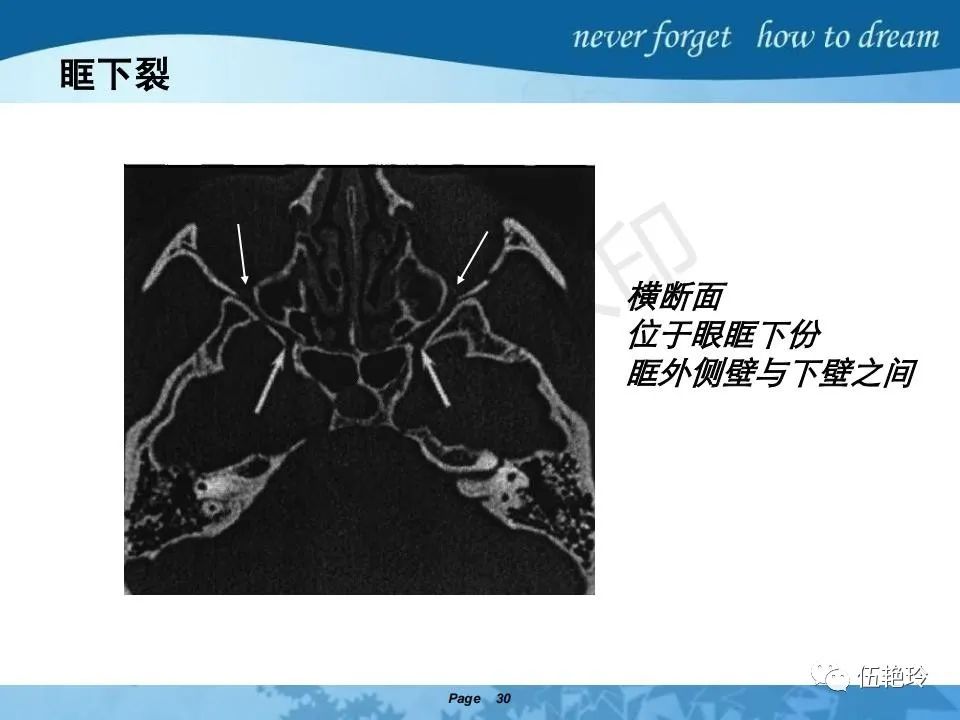

2.2 鼻咽特有的解剖途径:鼻咽癌原发灶循序进展的总途径:鼻腔(47.8%)→翼腭窝(15.2%)→ 眶下裂(3.2%)→眶尖(1.2%)→海绵窦(0.6%)。

2.31 向上颅内:①鼻咽顶壁→破裂孔(岩尖、斜坡)→蝶窦、海绵窦;②鼻咽顶壁→蝶骨基底部→蝶窦、海绵窦;③鼻咽侧壁→茎突前间隙→蝶骨大翼(卵圆孔)→海绵窦;④鼻咽侧壁→茎突前间隙→翼腭窝→ 颞下窝;⑤鼻咽前壁→鼻腔→翼突、翼腭窝→眶下裂→眶尖→海绵窦;⑥鼻咽前壁→鼻腔→上颌窦、筛窦;